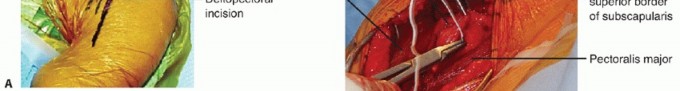

FIG 1 • A. Deltopectoral incision. B. Axillary incision beginning inferior to the tip of the coracoid and progressing toward the anterior axillary fold. C. In this dissection, the subscapularis tendon is being tagged at the superior border of the rotator interval.

The superior border of the subscapularis muscle blends in with the fibers of the supraspinatus muscle in the rotator interval (FIG 1C).

The tendon of the subscapularis is tagged with stay sutures.